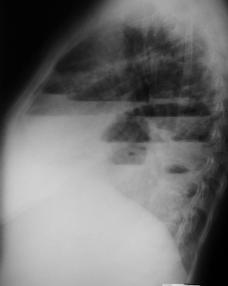

• Radiología del Tórax

Rx. tórax. PA y Lateral Izquierda

Rx. Tórax al momento de su Ingreso. radiopacidad difusa del hemitorax izquierdo conteniendo asas delgadas dilatadas con edema de la pared intestinal, desviación mediastinica contra lateral, disminuyendo por compresión del volumen torácico derecho, en la Rx lateral imágenes de niveles hidro-aereos múltiples , con discontinuidad diafragmática izquierda.